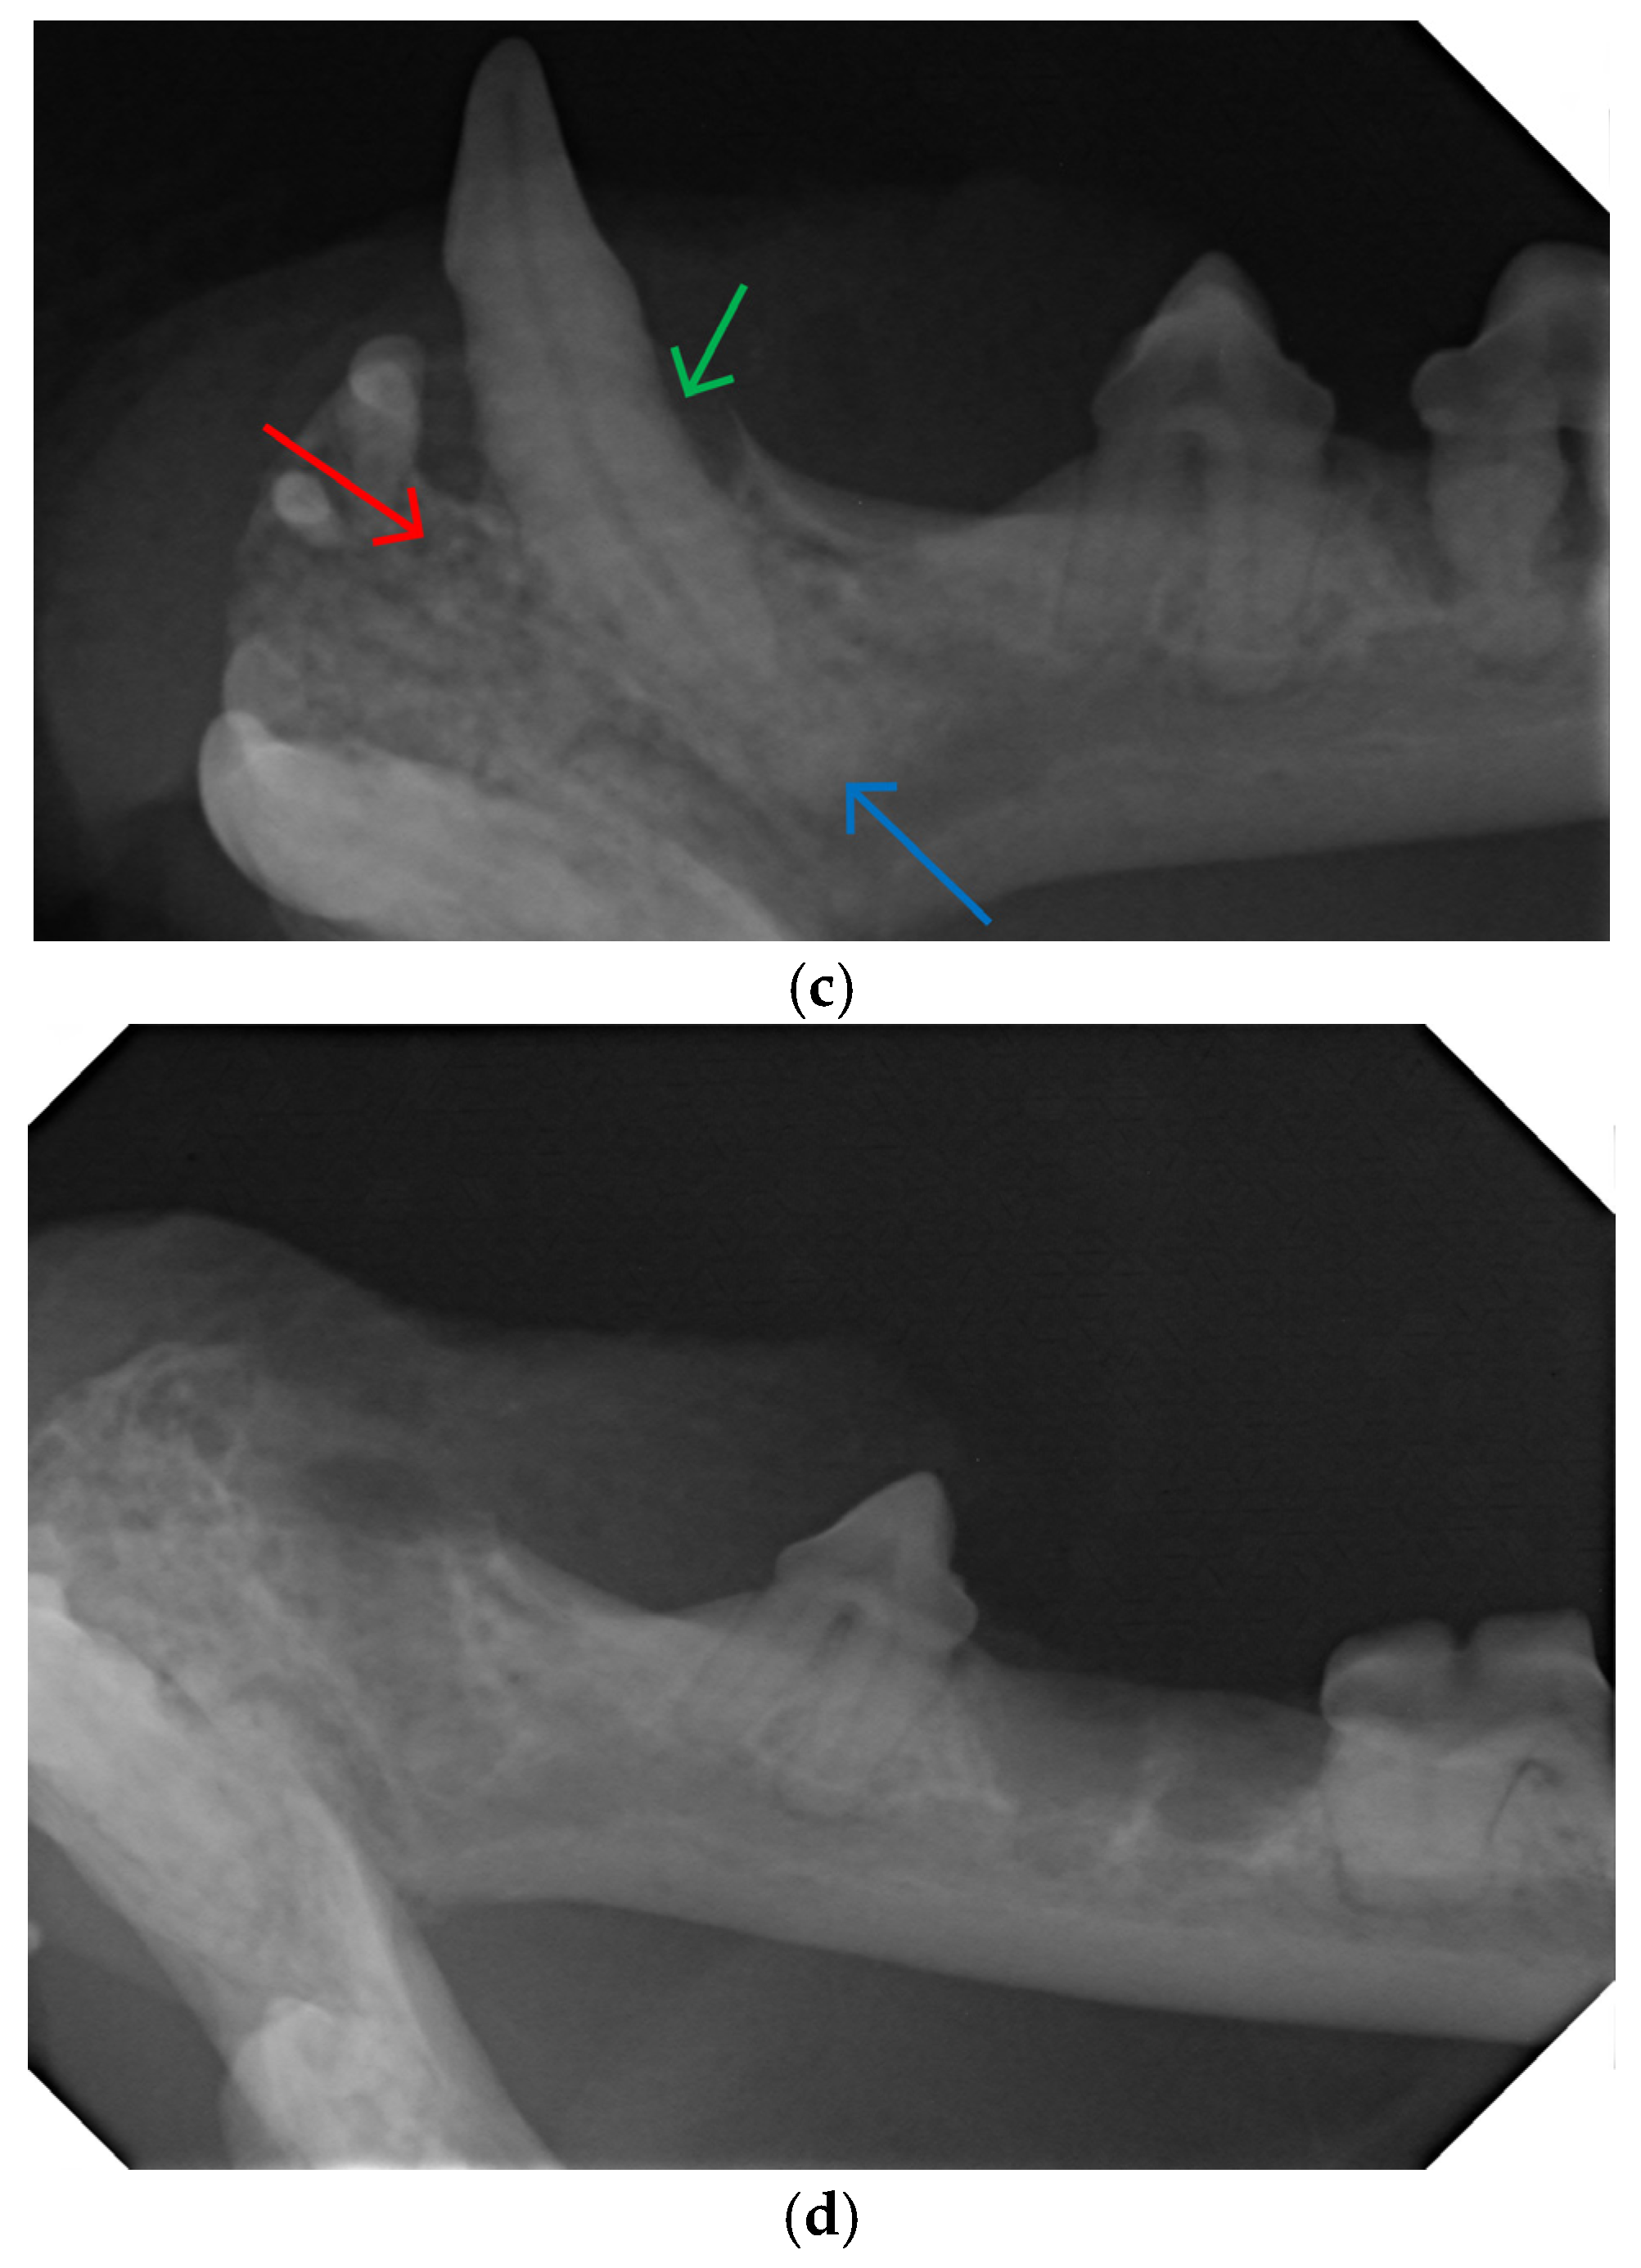

2.2. Dental Examination and Radiography

2.3. Dental Treatment